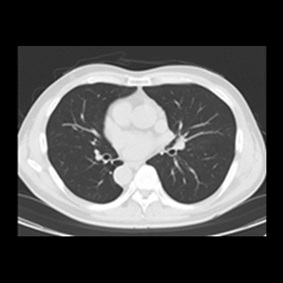

CT検査とは多方向からX線を照射し、身体の断面を撮影する検査です。

また、撮影した画像を重ね合わせることにより立体画像を構築し、より細かい診断ができます。

そして、CT検査では病変の存在、形態や性状などをより詳しく描出させるため、

臓器や血管にコントラストをつける造影剤という薬剤を用いて検査する場合があります。